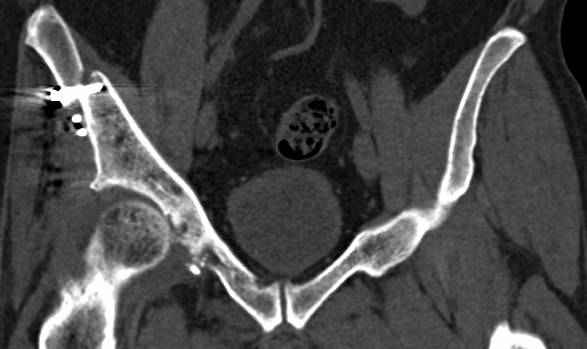

Интересно было бы посмотреть рентгенограммы до операции. У меня впечатление, что я не все вижу, что тут есть... Уважаемые Господа "тазисты" и "тазологи", к какому типу переломов вертлужной впадины по Летурнелю вы бы отнесли это случай?

Из переломов проходящих через крыло и/или заднюю стенку ни простой перелом "передней колонны" (явно имеется пером задней стенки, и не видно перелома седалищной или лонной), ни простой "поперечный", ни ассоциированный "Т-образный" (т.к есть перелом крыла и не видно перелома седалишной), ни ассоциированный "задняя колонна+задняя стенка", на ассоциированный "поперечный+задняя стенка", ни ассоциированный "передняя колонна+задняя гемисфера" (не видно перелома седалищной), ни ассоциированный "обе колонны" (не видно перелома лонной седалищной) не подходят под эту классификацию....

к таковым себя не причисляю, но...обычное дело для нашей страны - выкладывать 3D и не показывать стандартные проекции Judet. Дигност представляет те ракурсы, которые по-его мнению наиболее информативны, более того комп сам достраивает какие-то мелкие повреждения по 3D по своему усмотрению. По данной реконструкции можно предполагать высокий двухколонный перелом с оскольчатыми передней и задней колоннами, оскольчатую высокую переднюю колонну с задним полупоперечником или одно из перечисленных с вовлечение КПС. У меня впечатление за второй вариант, но нужно обследовать нормально - проекции, сканы.

высылаю дополнительно сканы.

итак, второй вариант: высокий двухколонный с вовлечением КПС... Ни одно из основных повреждений не репонировано, кроме задней стенки. Скорее всего попытка реконструкции вертлуги сейчас будет очень травматичной и не очень эфективной, т.е. вероятный риск более значим, чем ожидаемая польза... Лучше подождать, и потом сразу эндопротез